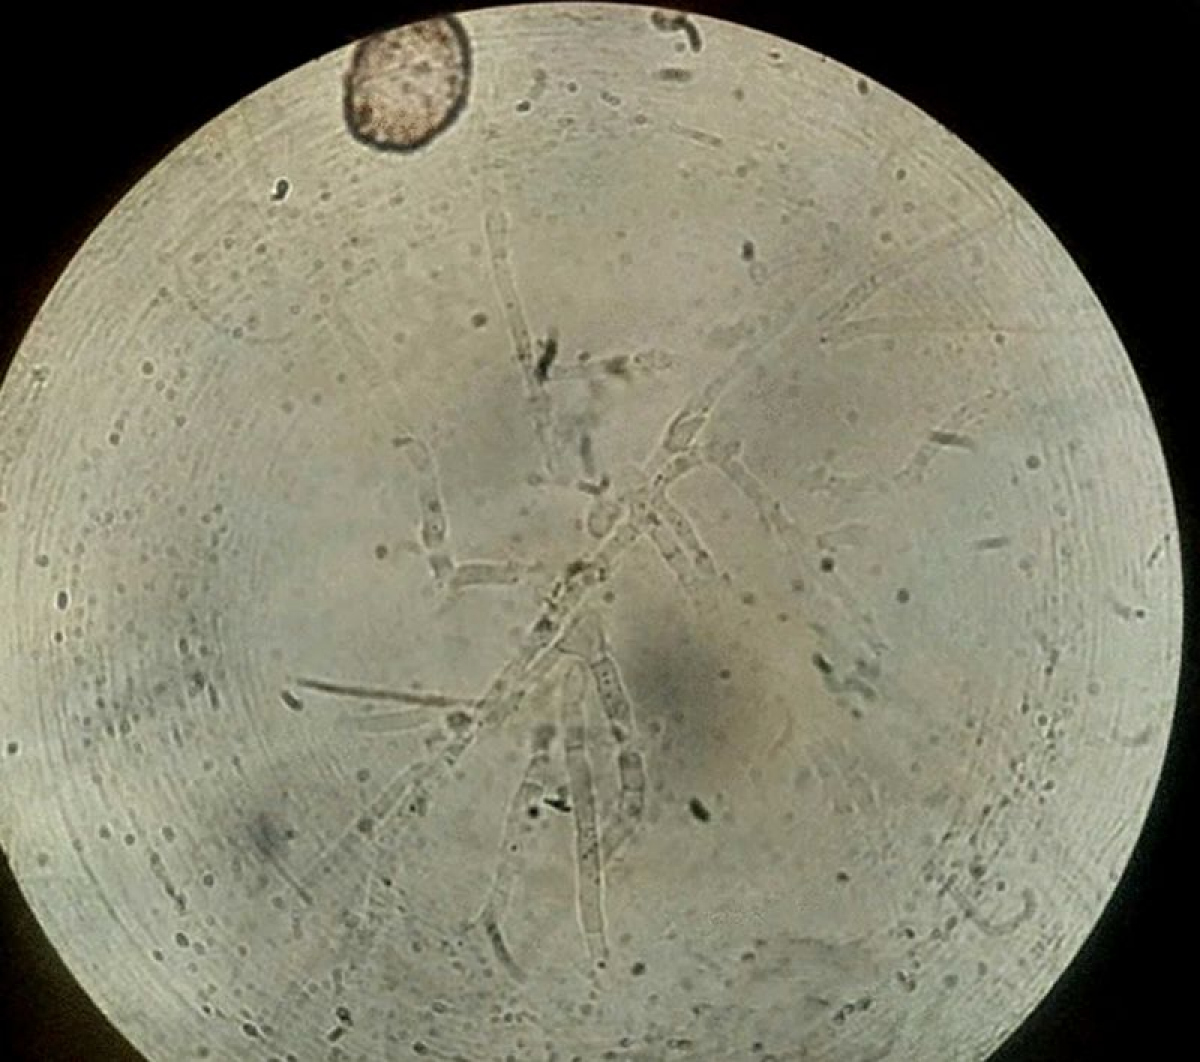

„K podezření, že se jedná o nový druh houby, došlo primárně podle sekvenace DNA vzorku houby izolované z iránského pacienta a po studiu genetických příbuzností s již známými druhy. Posléze bylo zjištěno, že příbuzné druhy vykazují i další odlišnosti. Například rozdíly v rychlosti růstu, zabarvení kolonií nebo velikosti a povrchové struktuře spor,” vysvětluje mikrobiolog a mykolog Vít Hubka.

Nedávno objevený druh Aspergillus hubkae patří do skupiny tzv. černých aspergilů, které se běžně vyskytují v půdě, ovzduší i na potravinách. Využívají se například k výrobě kyseliny citronové nebo k fermentaci potravin a nápojů, včetně populárního čínského čaje Pu-erh.